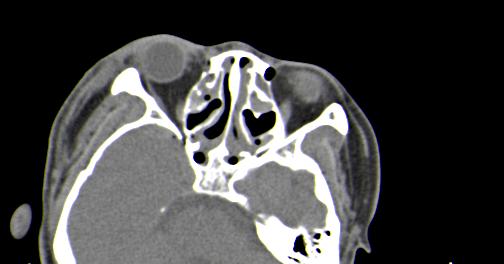

以下是引用皎皎白驹在2006-11-29 8:48:00的发言:[br]影像表现:双侧筛窦和上颌窦、鼻腔内均密度增高,右侧视神经增粗、弯曲,左筛窦顶部筛板及右侧纸板近视神经孔区可见骨折线。[br]结合临床表现考虑:右侧筛窦纸板近视神经孔区骨折致右侧视神经损伤。最好做个眼眶冠状扫描,更明确右侧视神经管是否狭窄。

以下是引用w_jianhua在2006-11-29 10:07:00的发言:[br]影像表现:双侧筛窦和上颌窦、鼻腔内均密度增高,右侧视神经增粗、弯曲,左筛窦顶部筛板及右侧纸板近视神经孔区可见骨折线。[br]结合临床表现考虑:右侧筛窦纸板近视神经孔区骨折致右侧视神经损伤。最好做个眼眶冠状扫描,更明确右侧视神经管是否狭窄。 [br] [br]支持[br]

以下是引用守望可可西里在2006-11-29 9:46:00的发言:[br][quote]以下是引用皎皎白驹在2006-11-29 8:48:00的发言:[br]影像表现:双侧筛窦和上颌窦、鼻腔内均密度增高,右侧视神经增粗、弯曲,左筛窦顶部筛板及右侧纸板近视神经孔区可见骨折线。[br]结合临床表现考虑:右侧筛窦纸板近视神经孔区骨折致右侧视神经损伤。最好做个眼眶冠状扫描,更明确右侧视神经管是否狭窄。